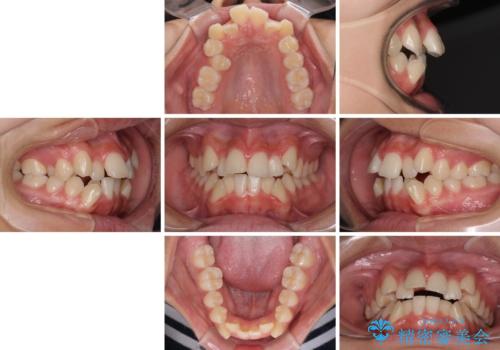

上顎骨幅が狭い 急速拡大装置を併用した抜歯矯正

- 歯列全体の叢生を気にして来院された患者様です。

検査を行った結果、上顎骨の横幅が相対的に狭いことが分かり、叢生が強いことから、急速拡大装置にて上顎骨を側方に拡大することで、叢生の解消と奥歯の咬み合わせ改善を図ることとしました。

一般的には上下左右の第一小臼歯4本を抜歯する必要がありますが、拡大量によっては非抜歯矯正の適用となる可能性があるため、まずは非抜歯矯正で治療を開始し、抜歯が必要と判断された時点で速やかに4本抜歯を行うこととしました。

急速拡大後、歯列はきれいに並んだのですが、口元が出っ歯になってしまったため、速やかに抜歯を行い、治療期間がいたずらに遅延することのないようにしました。